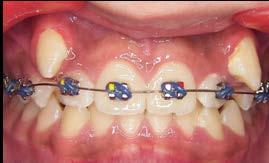

Adherencia a las indicaciones del tratamiento ortodóntico en pacientes con aparatología fija

La adherencia al tratamiento se define como el grado de comportamiento de una persona para seguir las recomendaciones sugeridas por el prestador de servicios de salud, en este caso, el ortodoncista. La adolescencia se considera una etapa idónea para recibir tratamiento de ortodoncia, ya que durante este periodo se presentan cambios fisiológicos, estructurales y anatómicos relacionados con el crecimiento y desarrollo de la cara y de las arcadas dentarias; sin embargo, uno de los principales retos es lograr y mantener una adecuada conexión con el paciente para obtener resultados favorables en la mejora de su oclusión. Objetivo: Evaluar el nivel de adherencia al tratamiento con aparatología fija en pacientes adolescentes del Instituto Bioprogresivo de Ortodoncia. Metodología: Estudio transversal con muestreo por conveniencia. Se evaluó el nivel de adherencia al tratamiento en pacientes atendidos en el Instituto mediante un cuestionario validado de autorreporte, aplicado durante los meses de agosto a diciembre de 2024. Se realizó un análisis descriptivo de la muestra y posteriormente se evaluó la frecuencia de reporte de los ítems. Resultados: El 81.7% de la muestra reportó haber recibido indicaciones higiénicas; el 85.3% recordó las instrucciones dietéticas recibidas; el 96.4% acudió a sus citas en la fecha y hora convenidas; el 97.5% refirió dar seguimiento a su tratamiento, aun cuando ya se sentían satisfechos con los resultados; el 92.6% solicitó consulta inmediata cuando se desprendió algún bracket; el 96.4% siguió las indicaciones incluso al salir de viaje; el 91.5% consultó oportunamente al ortodoncista ante la presencia de alguna molestia; el 92.6% recordó las fechas de sus próximas consultas, y solo el 2.5% reportó haber tenido conflictos con su ortodoncista. Conclusión: La adherencia de los pacientes al tratamiento de ortodoncia en la muestra fue adecuada; no obstante, es importante evaluar de forma constante este aspecto para verificar la motivación del paciente adolescente, evitar la deserción prematura del tratamiento y prevenir posibles complicaciones.

Palabras clave: adherencia, adolescentes, indicaciones, ortodoncia.

Las maloclusiones son consideradas un importante problema de salud pública. De acuerdo con la Organización Mundial de la Salud (OMS), estas constituyen el tercer problema de salud bucal más relevante, después de la caries dental y las enfermedades periodontales.1 Se estima que, en México, alrededor del 60% de la población presenta alguna de estas condiciones.2 Las maloclusiones son alteraciones en la posición de los componentes dentales o esqueletales del sistema estomatognático.3 Su efecto no es solo funcional y/o estético, sino que también influye en los aspectos psicosociales y en la calidad de vida de quienes las padecen.4

De acuerdo con la OMS, la adolescencia es el periodo comprendido entre los 10 y 19 años; en esta etapa se producen cambios físicos, psicológicos, biológicos, intelectuales y sociales que corresponden a la transición de la infancia al estado adulto.5 El abordaje de las maloclusiones se lleva a cabo mediante el tratamiento ortodóntico, en el cual se emplean distintos aditamentos con la finalidad de armonizar la oclusión y los rasgos faciales del tercio medio e inferior del rostro.6 La adolescencia es el momento preferido para realizar este tratamiento, ya que durante esta etapa la dentición permanente ha erupcionado, pero el crecimiento craneofacial aún puede aprovecharse.7

Para que el tratamiento ortodóntico sea exitoso, se requiere la cooperación del paciente en factores tales

como asistir a las citas, mantener una adecuada higiene oral, seguir las recomendaciones dietéticas, así como usar y cuidar los aparatos y aditamentos prescritos.8 Sin embargo, el tratamiento puede alterar las rutinas establecidas e interferir con las actividades sociales del paciente adolescente, además de repercutir en su autoestima debido a su aspecto físico. Por ello, resulta imperativo mantener una comunicación adecuada que permita comprender las necesidades y expectativas del paciente respecto al tratamiento y generar en este una adherencia adecuada a las indicaciones prescritas por parte del ortodoncista, a fin de favorecer el éxito del tratamiento.9

Resultados

Descripción de la muestra

En el estudio participaron 82 adolescentes; el 60.9% (n = 50) fueron mujeres, quienes presentaron una edad promedio de 15.3 ± 2.5 años. El 78.1% (n = 64) refirió que era la primera vez que se encontraba bajo tratamiento ortodóntico.

Adherencia al tratamiento

De acuerdo con la encuesta de adherencia en pacientes adolescentes bajo tratamiento ortodóntico, el 81.7% de la muestra reportó haber recibido

indicaciones higiénicas; el 85.3% recordó las instrucciones dietéticas recibidas; el 96.4% acudió a sus citas en la fecha y hora convenidas; el 97.5% refirió dar seguimiento a su tratamiento, aun cuando ya se sentían satisfechos con los resultados; el 92.6% solicitó consulta inmediata cuando se desprendió algún bracket; el 96.4% siguió las indicaciones incluso cuando salieron de viaje; el 91.5% consultó de manera oportuna al ortodoncista ante la presencia de alguna molestia; el 92.6% recordó las fechas de sus próximas consultas y solo el 2.5% reportó haber tenido conflictos con su ortodoncista (Tabla 2).

Discusión

En este estudio se encontró que fue frecuente el reporte afirmativo de las conductas requeridas por parte del paciente adolescente a lo largo de su tratamiento, ya que en todos los ítems más del 80% de la muestra reportó adherencia a las indicaciones del tratamiento. Estos resultados contrastan con el estudio en el cual se validó el instrumento, donde la adherencia fue intermedia, debido a que las conductas requeridas solo se reportaron en aproximadamente el 50% de la muestra.11